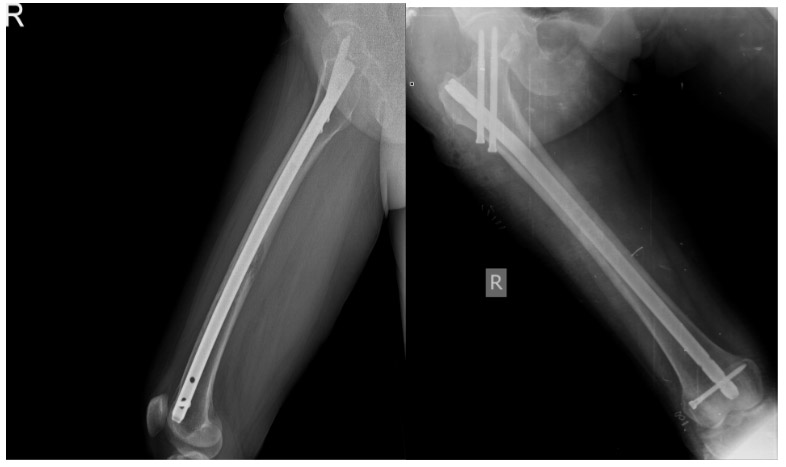

Post-surgery: The X-ray shows a titanium nail completely filling the inside of the femur.